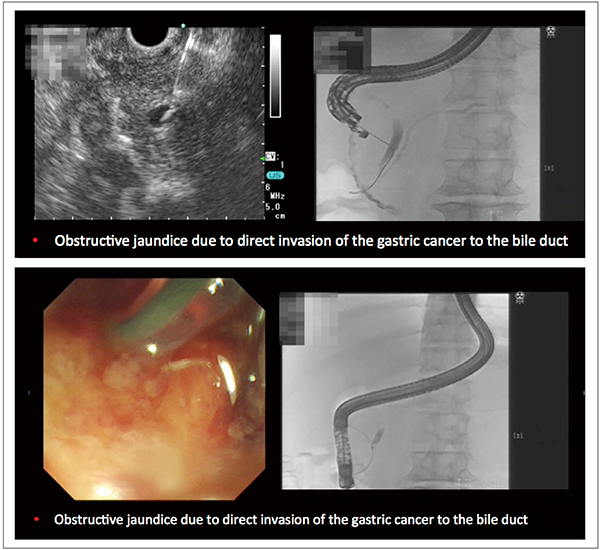

胆管挿管困難例に対して近年、注目されているのがEUS-rendezvous法である。これは、EUSで胆管を穿刺して、ガイドワイヤを乳頭に出し、そのガイドワイヤを利用してERCPを行う方法である。岐阜大学の岩下拓司先生からご提供いただいた症例を供覧する(図12)。胃がんの十二指腸浸潤で乳頭の正面視がまったくできないため、十二指腸下行部から膵内胆管を穿刺した後、ガイドワイヤを乳頭から出し、ここでスコープを十二指腸鏡に入れ替えて、ガイドワイヤ越しにERCPカニューラを挿入して胆管ステント留置を行っている。なお、本症例では、ガイドワイヤの把持にスネアを用いたが、最近は把持鉗子や生検鉗子を用いることが多い。

図12 EUS-rendezvous法を用いた症例

(動画ご提供:岐阜大学・岩下拓司先生)

(参考文献4)より引用)